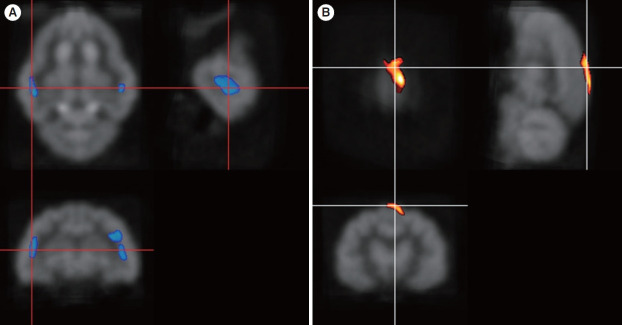

Results: Four months after hearing loss, the auditory cortical area's activity decreased, and activity in the associated visual area increased. After 7 months of cochlear stimulation, the superior marginal gyrus and cingulate gyrus, which are components of the default mode network, showed hypermetabolism. The inferior colliculi showed hypometabolism.

Conclusion: Resting-state cortical activity in the default mode network components was elevated after cochlear stimulation. This suggests that the animals' awareness level was elevated after hearing restoration by the cochlear implantation.